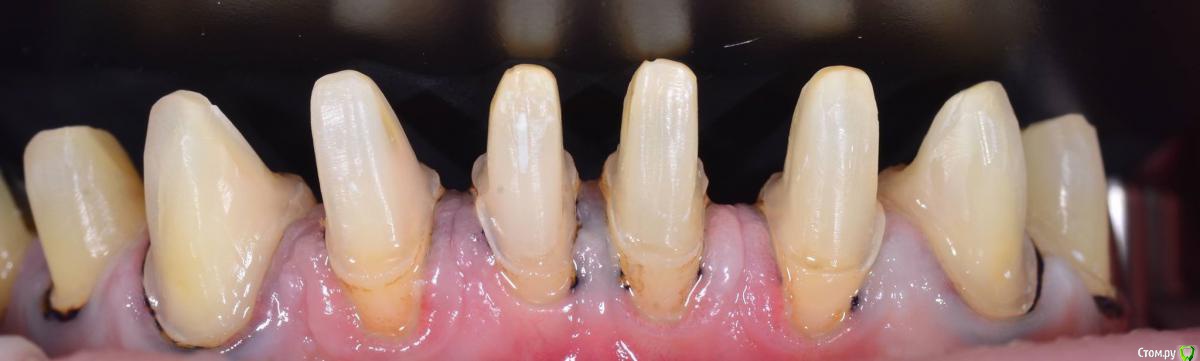

AndyAndy Опубликовано 5 апреля, 2016 Поделиться Опубликовано 5 апреля, 2016 Такое ощущение, судя по фото, что абатменты полированные. Техник не проводит пескоструйную обработку супрагингивальной части абатмента? Ссылка на комментарий

Карен Аванесов Опубликовано 5 апреля, 2016 Поделиться Опубликовано 5 апреля, 2016 есть ли фото с язычной стороны? Ссылка на комментарий

togrul Опубликовано 5 апреля, 2016 Автор Поделиться Опубликовано 5 апреля, 2016 Такое ощущение, судя по фото, что абатменты полированные. Техник не проводит пескоструйную обработку супрагингивальной части абатмента?Да абатменты такие пришли с фрезерного центра. Проблем небыло с фиксацией. Ссылка на комментарий

togrul Опубликовано 5 апреля, 2016 Автор Поделиться Опубликовано 5 апреля, 2016 есть ли фото с язычной стороны? Есть фото только вч Ссылка на комментарий